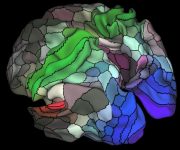

Enerjinin azaldığını hissettiğimizde, bunu çoğu zaman yaşlanmanın kaçınılmaz bir sonucu olarak kabul etmeye meyilliyiz. Oysa bilim, bu basit anlatının gerçeği tam olarak yansıtmadığını söylüyor. Enerji, yaşla birlikte yok olmuyor; biçim değiştiriyor, yeniden örgütleniyor, bedenin ve hayatın talepleriyle yeni dengeler kuruyor. 509. sayımızın kapağını bu nedenle “Bedenin Gizli Mantığı” dosyasına ayırdık. Birbiriyle konuşan iki yazı, bedenin sandığımızdan çok daha zeki, uyumlu ve stratejik bir sistem olduğunu gösteriyor. İlki, 20’li yaşlarda bol ve affedici olan enerjinin neden 40’larda zorlandığ...[Devamını gör...]